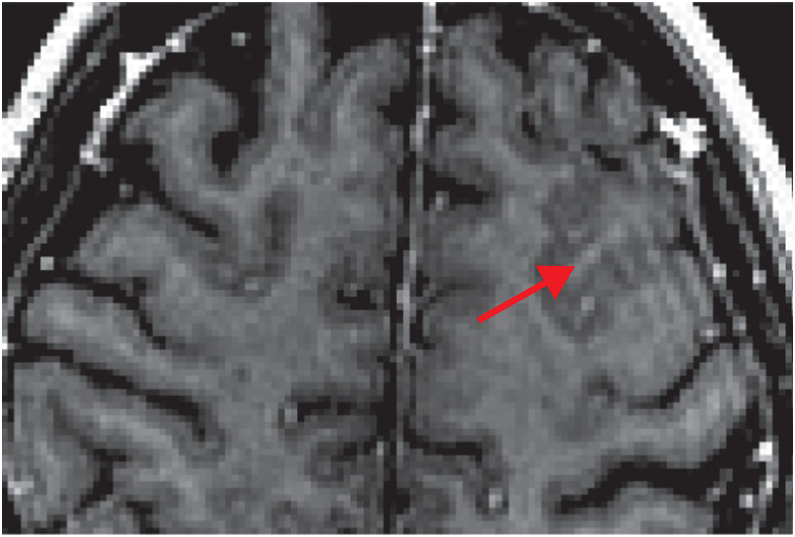

Meningeal lymphatics clear erythrocytes that arise from subarachnoid hemorrhage

The Radiology Assistant : Non-traumatic Intracranial Hemorrhage

Vasospasm and p53-Induced Apoptosis in an Experimental Model of Subarachnoid Hemorrhage